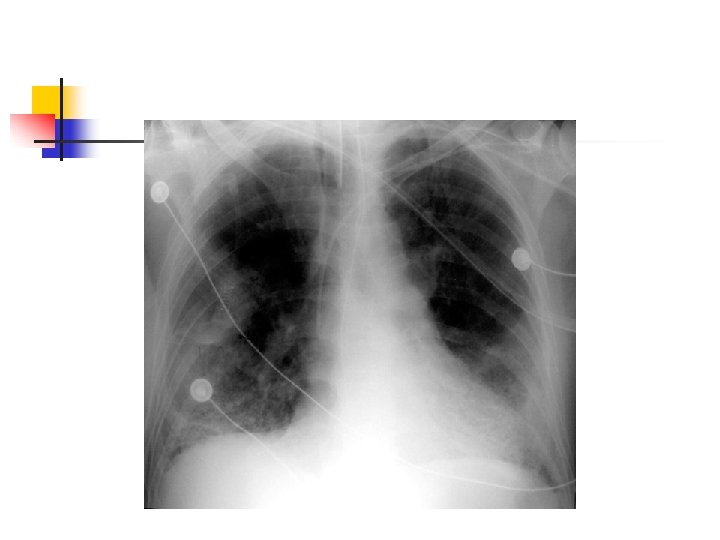

Pneumonia n Inflammation & infection of lunginfecting organisms typically inhaledorganisms transmitted to lower airways and alveoli causing inflammation- impairs gas exchange Etiology: bacteria, virus, Mycoplasma, fungus, or from aspiration or inhalation of chemicals or other toxic substances n Risk factors: cigarette smoking, chronic underlying disorders, severe acute illness, suppressed immune system, & immobility

Pneumonia Diagnostic: n Sputum and blood cultures, CBC, ABGs, CXR, & Bronchoscopy Nursing Diagnoses: n Ineffective airway clearance r/t thick, tenacious sputum n Ineffective breathing pattern r/t tachypnea, chest pain, & airway inflammation n Impaired gas exchange r/t exudate in alveoli n Activity intolerance r/t hypoxemia, fatigue n Acute pain r/t disease process n Imbalanced nutrition less than body required

ARDS - Diagnostics Arterial Blood Gas n Blood Tests n Blood and Urine cultures n Bronchoscopy n Chest x-ray n Sputum culture and analysis

Diagnosis Method CT n Chest X ray n Encourage exercise to improve resp. fitness n Counsel to avoid respiratory irritants and stop smoking n Immunize against common flu and pneumonia Pharmacology: n Antibiotic therapy- Tequin, Levaquin n Bronchodilators- Albuterol, Combivent, Theophylline n